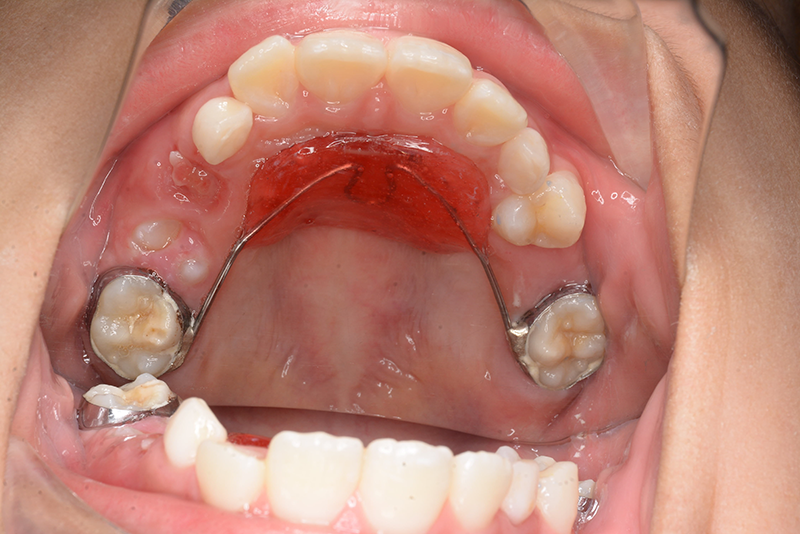

| 使用装置 | GMD、Nanceホールディングアーチ | ||||||

| 口腔内所見 | over jet 2.5mm、over bite 2.0mm、右側大臼歯関係はEnd on class Ⅱ、上顎左側Eは早期喪失により左側大臼歯関係はFull classⅡ、右側Eは6の異所萌出により歯根吸収が進行したため一般歯科医院にて抜去済みであった。 |

| パノラマ所見 | 上顎両側6、特に左側6は近心傾斜が認められ、両側5の萌出スペース不足が認められた。 |

| 批評・予后 | 早期に6の遠心移動を行いナンスのホールディングアーチにて保隙をした結果、5は良好な状態で萌出できたように思う。 今後は永久歯列完成まで経過観察を行っていく予定である。 |